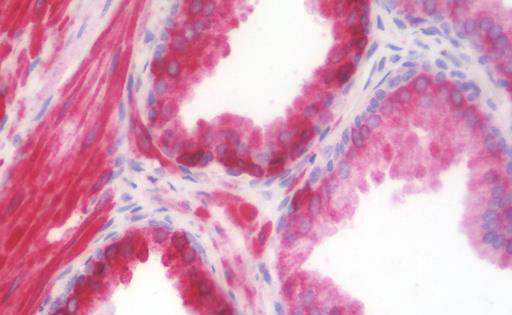

Anti-AGR2 antibody IHC staining of human prostate. |